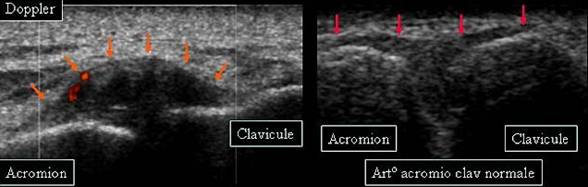

ENTORSA ACROMIOCLAVICULARA

Epansament hipoecogen in sistemul capsulo-ligamentar→

Cu discreta hiperemie la Doppler

Comparatie cu aspectul normal al articulatiei→

Radiografic- aspect normal →